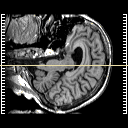

MR Study #1 -- Slice #60

[Home][Help][Clinical] Slice 60